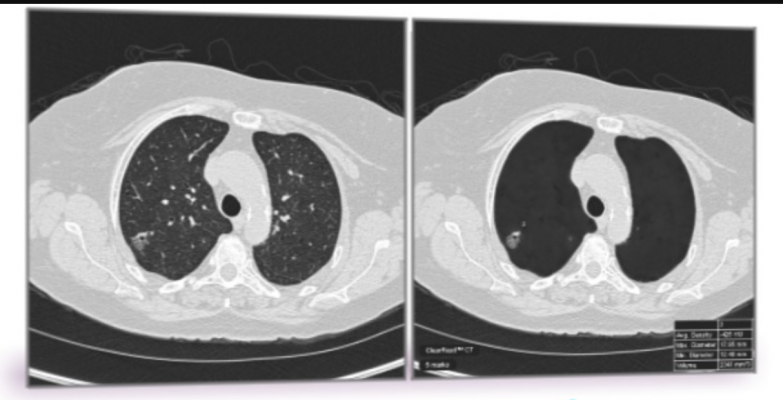

November 11, 2020 — Low-dose computed tomography (CT) screening methods may prevent one death per 250 at-risk adults screened, according to a meta-analysis of eight randomized controlled clinical trials of lung cancer screening. Researchers at the University of Georgia analyzed the health outcomes of 90,275 patients, comparing those who were screened versus those who received usual medical care or chest x-rays. Their analysis found a clinically and statistically significant 0.4 percent reduction in lung cancer-caused death long term, which translates into one preventable death per 250 at-risk adults screened. The authors recognize the important potential harm of overdiagnosis in cancer screening programs, and there was some evidence of overdiagnosis due to increased incidence in the screened group. However, based on the reduction in all-cause mortality being in the same direction and magnitude as lung cancer mortality, the authors interpret that the associated harms "do not appear to increase other causes of mortality," and the results of the study align with the U.S. Preventive Services Task Force recommendations for CT-based lung cancer screenings for adults age 55 to 80 who have a history of regular smoking.